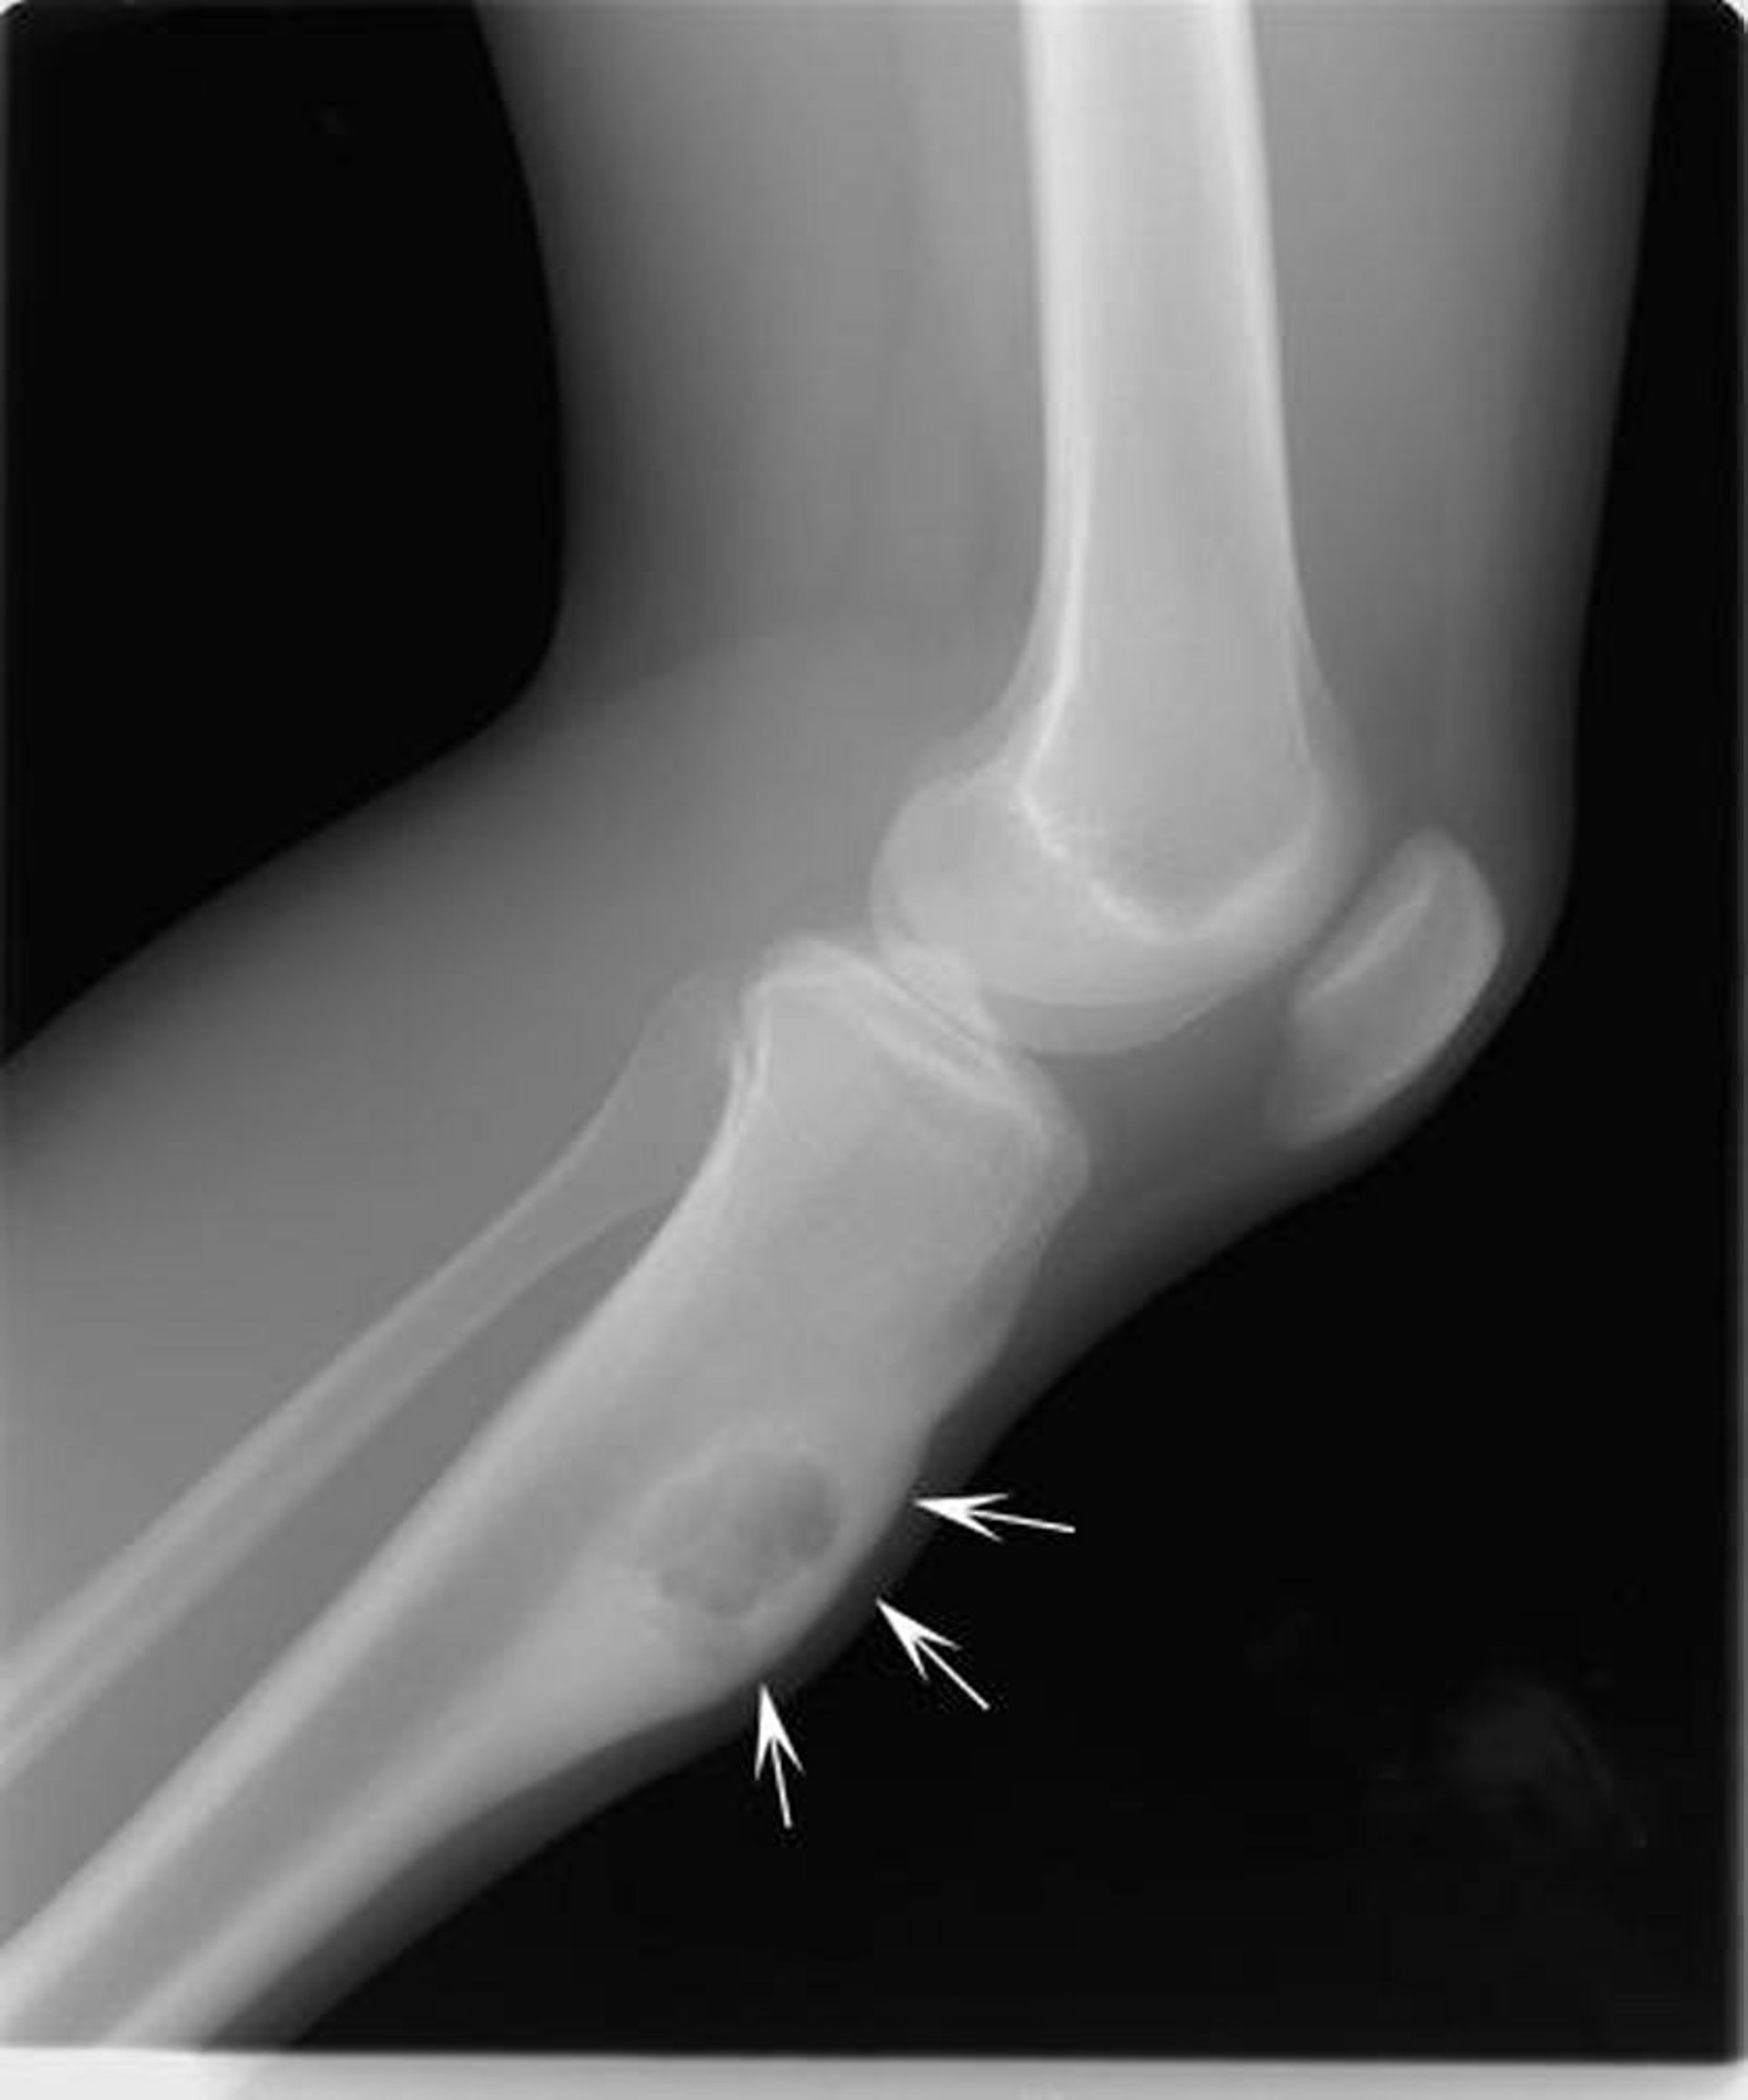

Fibroma condromixoide

Essa radiografia do joelho mostra fibroma condromixoide na tíbia abaixo do joelho (setas), expandindo a parte anterior do osso.

Imagem cedida por cortesia de Michael J. Joyce, MD, and Hakan Ilaslan, MD.